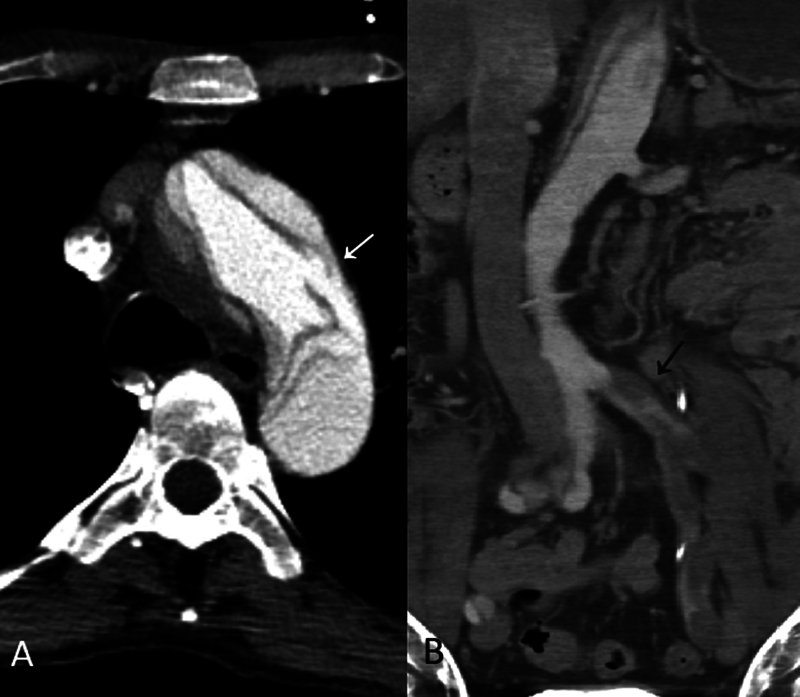

The distal extent of aortic repair in acute aortic dissection and the management of malperfusion in terms of timing and strategy are still debated topics. We present a case of acute type B dissection with retrograde extension to the ascending aorta, with the most proximal intimal tear in the descending thoracic aorta, associated with both early lower extremity and delayed mesenteric malperfusion syndrome, treated effectively by femoral artery open fenestration and hybrid zone 2 arch repair.